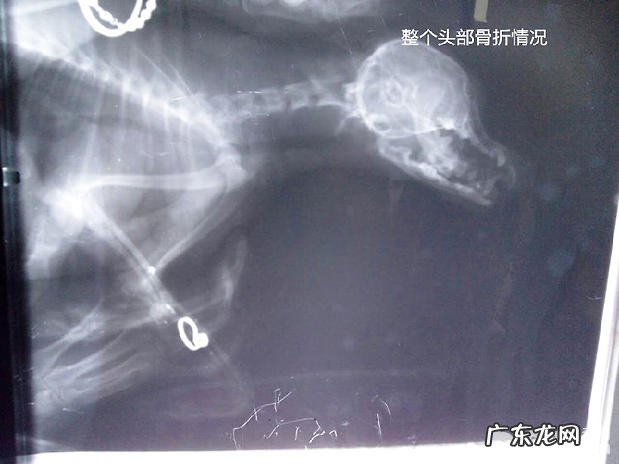

普遍的骨裂一般全是前腿或是后腿骨折,可是近期门诊所来啦一只是头骨中的下颌骨裂,而且牙根爆出,这是由于这只小狗和别的狗狗打架导致的結果 。从图上能够明显的见到全部头顶部头骨的状况 。下下颌骨裂是额骨骨裂中最普遍的一种,无论小动物尺寸都能够产生 。下颌骨折的症状有流血和发胀,强烈痛疼,进食很艰难,长此以往,小动物会出現削瘦,缺乏营养,并且还会继续从裂口处排出脓性分泌物 。这类骨裂的治疗方法都不除外,也是开展手术治疗固定不动 。

头顶部骨裂的X光片